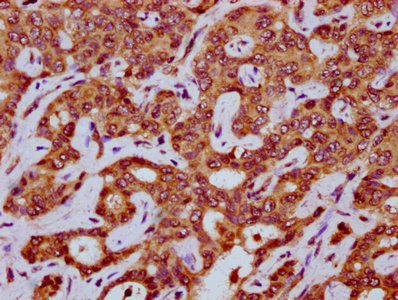

IHC image of CSB-PA773606LA01HU diluted at 1:200 and staining in paraffin-embedded human liver cancer performed on a Leica BondTM system. After dewaxing and hydration, antigen retrieval was mediated by high pressure in a citrate buffer (pH 6.0). Section was blocked with 10% normal goat serum 30min at RT. Then primary antibody (1% BSA) was incubated at 4°C overnight. The primary is detected by a biotinylated secondary antibody and visualized using an HRP conjugated SP system.